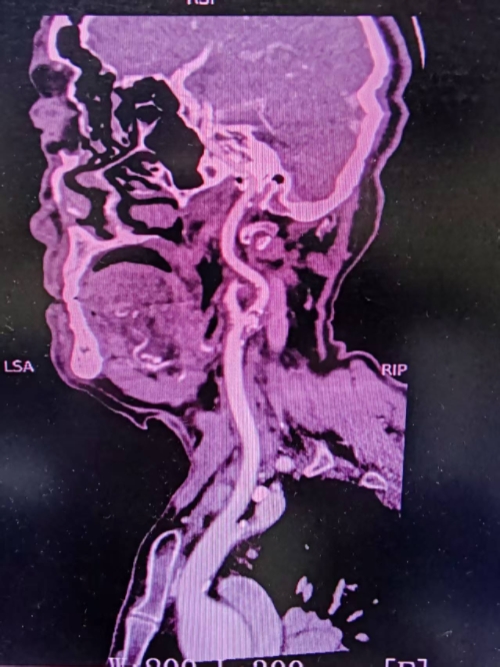

团队对患者进行了全方位的影像学评估,通过高分辨率血管成像技术及头颈CTA,精确研判了狭窄位置、斑块性质及颅内血流代偿情况,影像科逄利博主任为手术方案的制定提供了关键依据。深入的多学科讨论确保了手术策略的个性化与最优化,将“安全第一”的理念贯穿于术前规划的每一个环节。

术前颈动脉血管重度狭窄伴有易脱落粥样硬化斑块